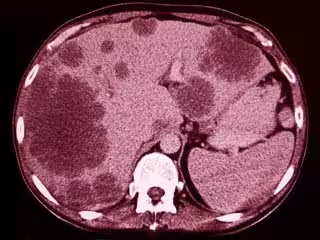

Una pequeña proteína podría ser la clave de por qué las células madre permiten la metástasis

GETTY IMAGES/ISTOCKPHOTO / SEMNIC - Archivo